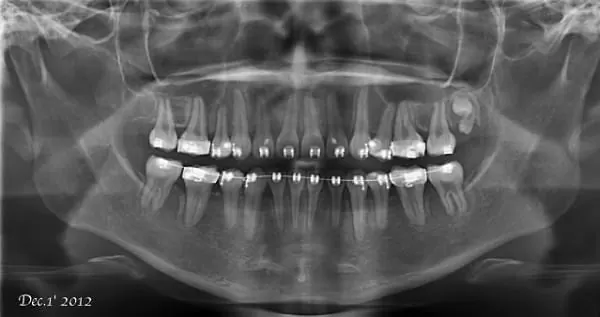

圖2.再利用矯正方式將牙齒重新排列整齊,並符合患者牙齒的咬合型態。

使用一般傳統矯正器將牙齒重新排列整齊。